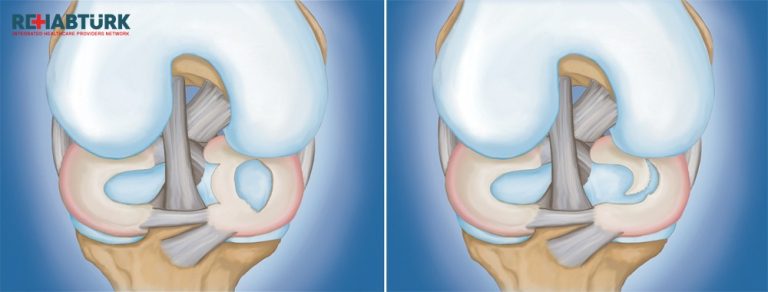

الركبتان هي المفاصل الأكثر تضررًا من هشاشة العظام (OA). يحدث التهاب مفصل الركبة عندما ينكسر الغضروف في الركبة ، والذي يمكن أن يحدث بسبب الشيخوخة أو زيادة الوزن أو الإصابة ، من بين أمور أخرى. تبدأ عملية المرض قبل ملاحظة…